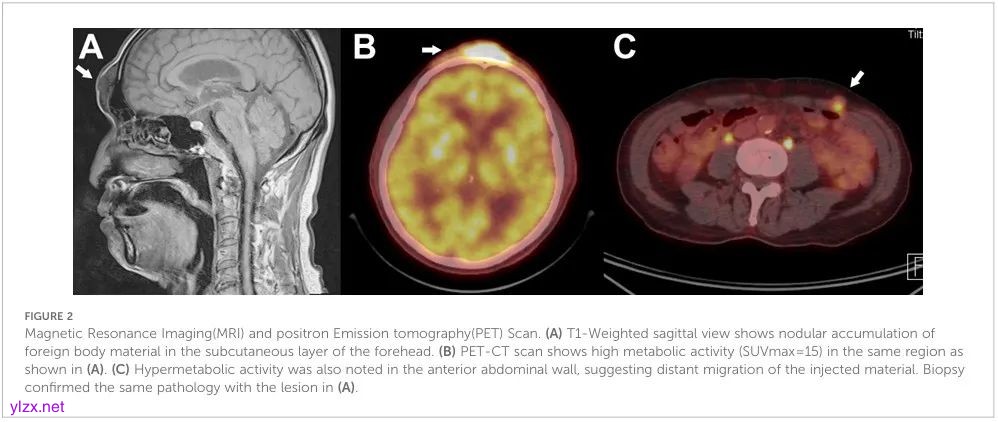

进行了进一步的系统检查。对比MRI显示眉间、鼻唇沟和下脸皮下有多处结节状软组织病变。(图2A)正电子发射断层扫描计算机断层扫描(PET-CT)显示,同一结节病变中存在强烈的代谢活动。(图2B)有趣的是,腹壁也有代谢活动,这增加了注射物质迁移的可能性(图2C)。

图2:磁共振成像(MRI)和正电子发射断层扫描(PET)扫描。(A) T1加权矢状切面显示前额皮下有结节状异物堆积。(B) PET-CT扫描显示,如(A)所示,同一区域的代谢活性很高(SUVmax=15)。(C) 在前腹壁也观察到高代谢活动,表明注射物质发生了远距离迁移。活检证实了与(A)中病变相同的病理。